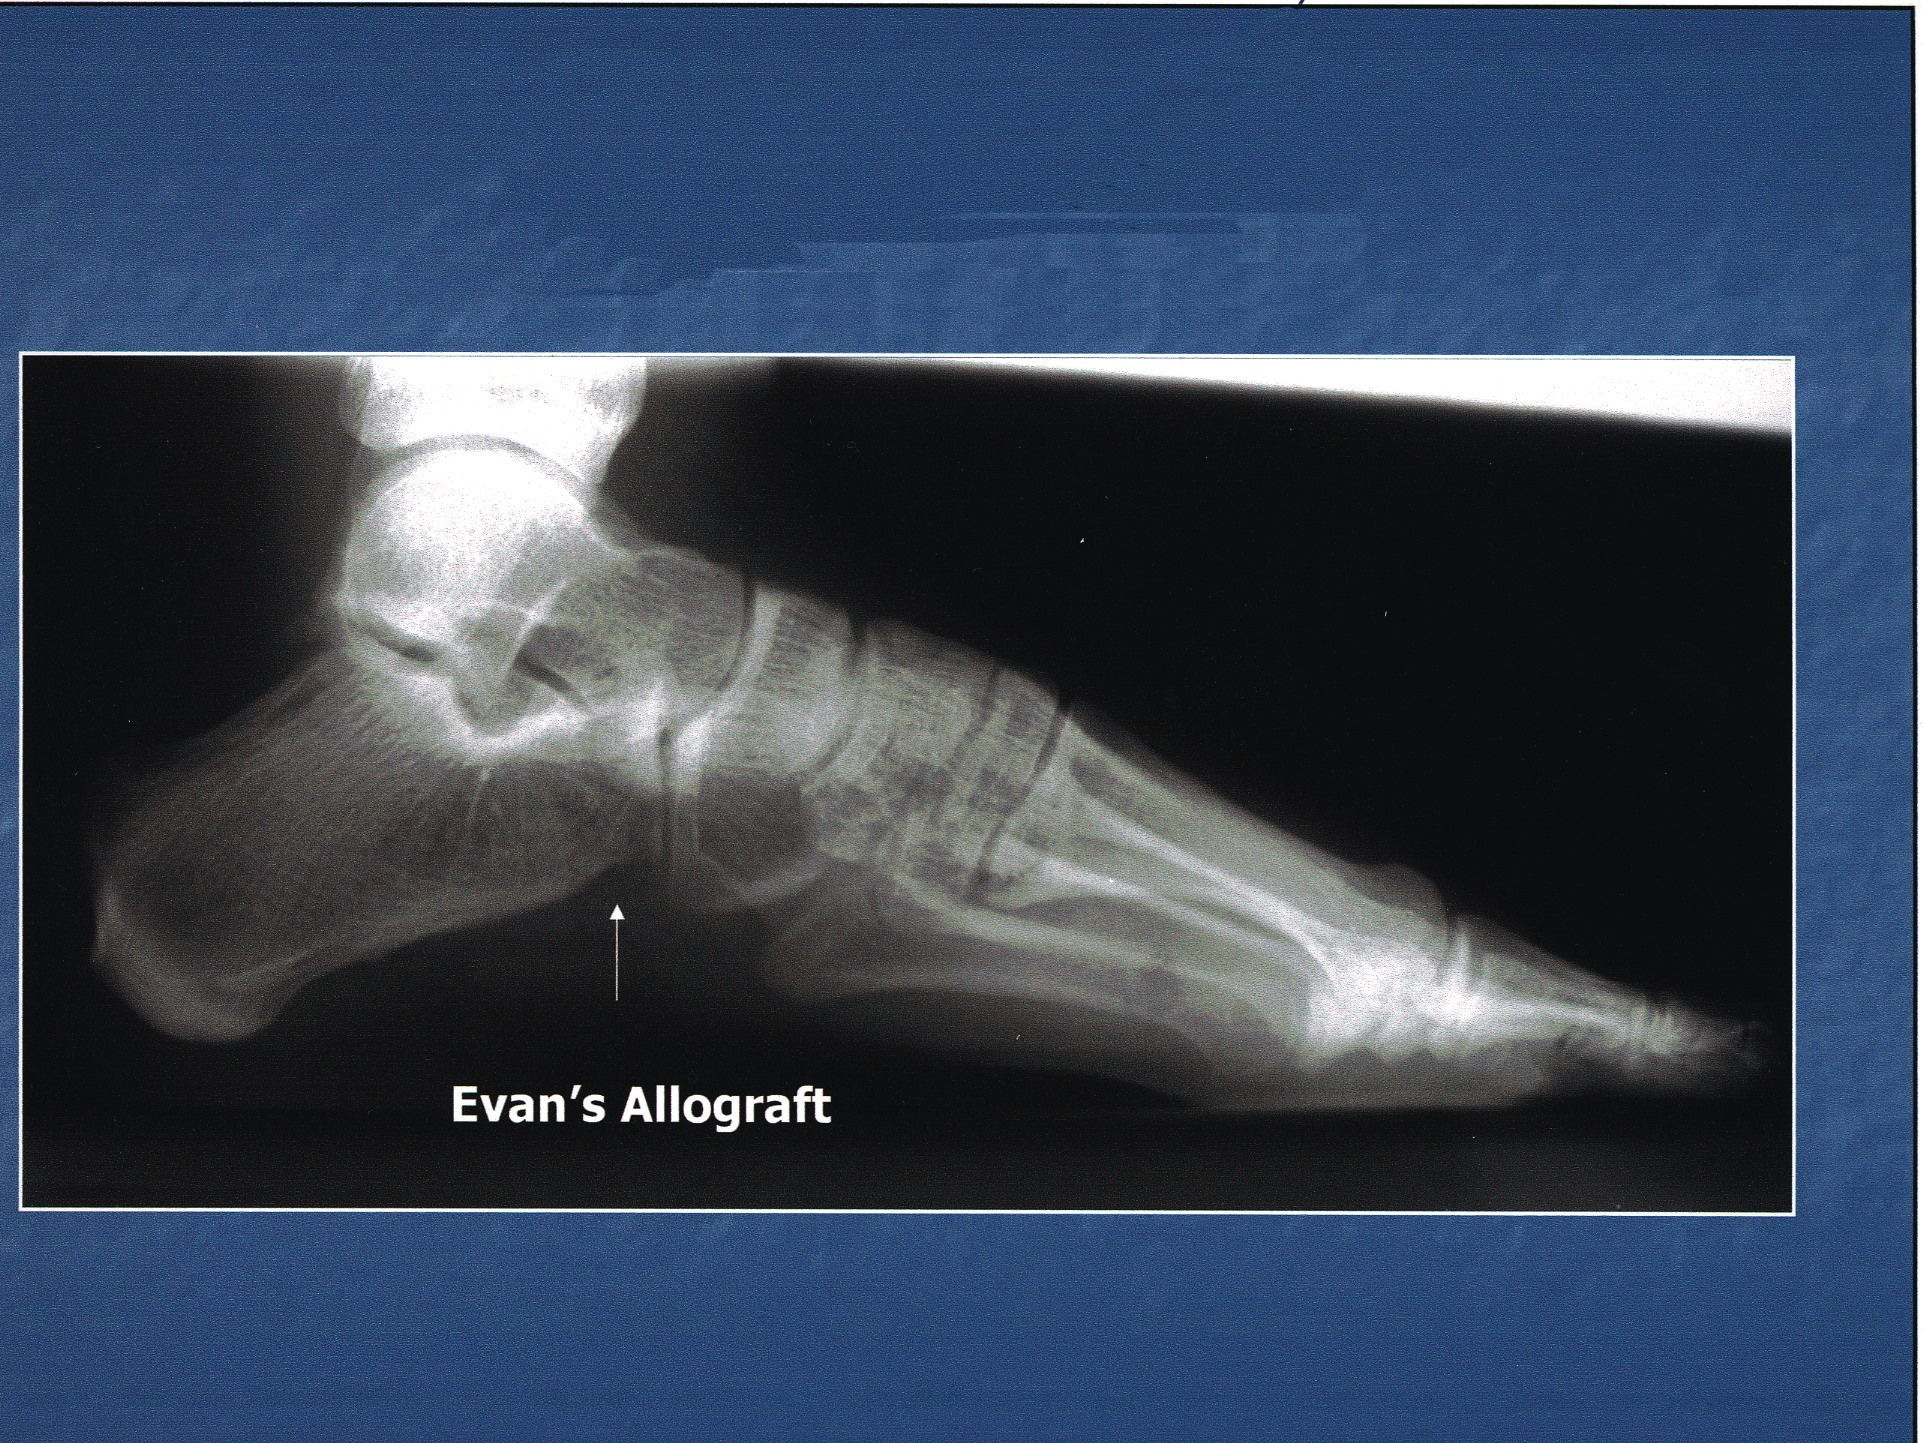

In this case, the patient presented with an end-stage Charcot midfoot with a chronic plantar ulceration and equinus deformity (see photo on the right). The correction entailed midtarsal joint arthrodesis, tendo-Achilles lengthening and local wound care.

Biologic and biophysical enhancement included an external bone stimulator, external fixation and tricalcium phosphate mixed with platelet gel concentrate and DBM. Final consolidation is evident at five months post-op (see photo on the left).